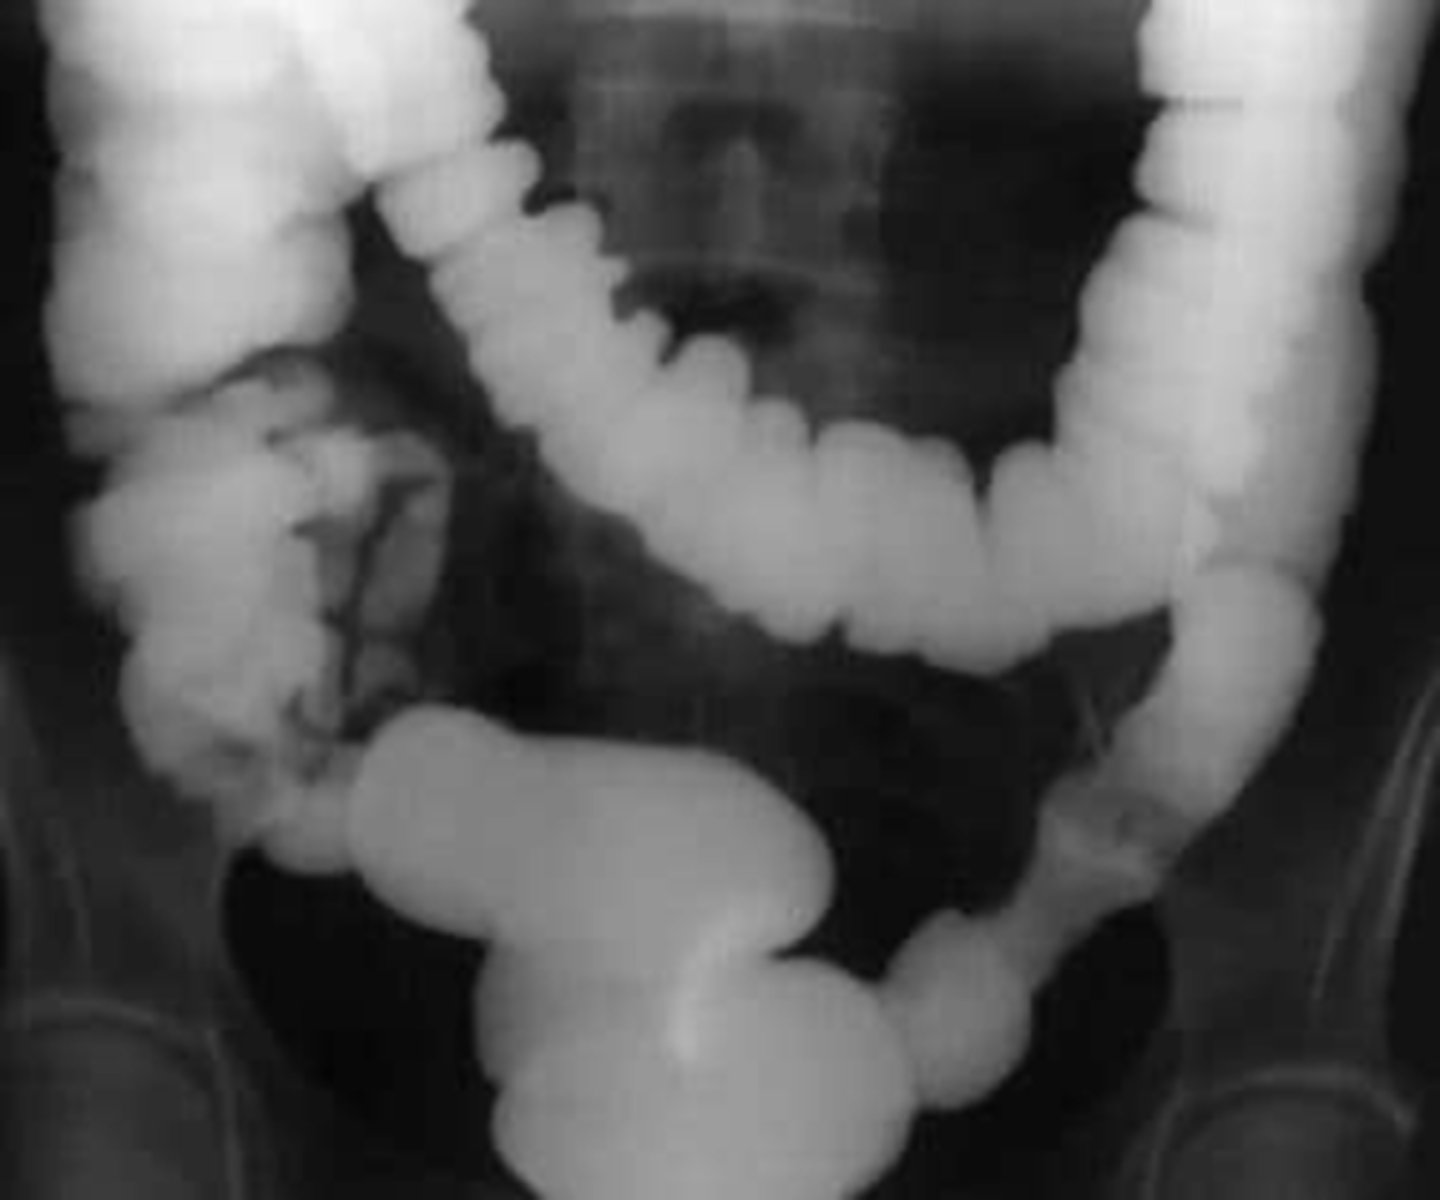

dilated loops of bowel air fluid levels

dilated loops of bowel

string of pearls sign- diagnostic of mechanical obstruction

stretch sign- small pockets of gas trapped bn valvulae conniventes within fluid filled bowel